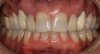

Figure 5d  Completed, porcelain-fused-to-gold implant restorations, custom gold abutments, lingual-set screw-retention, Kerr Extrude¬Æ light-body crown-abutment seal.

Figure 5d

Figure 5e  Completed, porcelain-fused-to-gold implant restorations, custom gold abutments, lingual-set screw-retention, Kerr Extrude¬Æ light-body crown-abutment seal.

Figure 5e

Figure 5f  Completed, porcelain-fused-to-gold implant restorations, custom gold abutments, lingual-set screw-retention, Kerr Extrude¬Æ light-body crown-abutment seal.

Figure 5f

Figure 5g  Completed, porcelain-fused-to-gold implant restorations, custom gold abutments, lingual-set screw-retention, Kerr Extrude¬Æ light-body crown-abutment seal.

Figure 5g